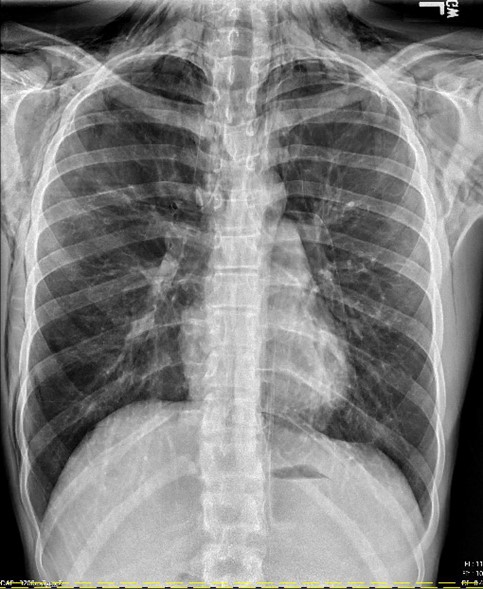

Initial Chest X-ray

Findings: There is extensive pneumomediastinum with air dissecting along the esophagus, mediastinum, and supraclavicular soft tissues, along the lateral chest wall bilaterally, greater on the right.

No definite pneumothorax is visualized.

There is no focal consolidation. There is no pleural effusion. The heart size is normal. The bones are unremarkable.

Impression: Marked pneumomediastinum with air dissecting across the soft tissue planes.